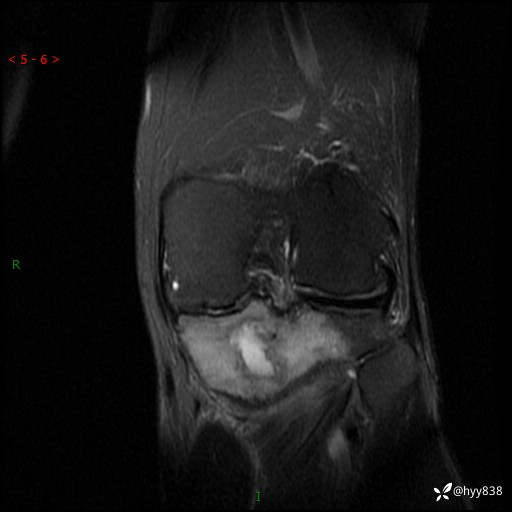

cor T2WIfs